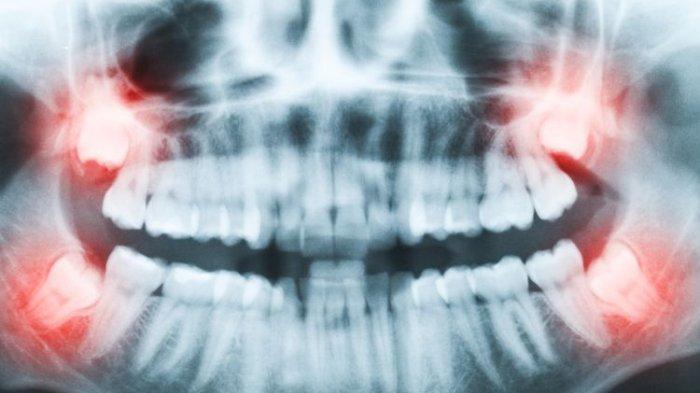

ilustrasi impaksi gigi

ilustrasi impaksi gigi (health.kompas.com)

Sedangkan pada pemeriksaan klinis atau objektifnya, nampak pada daerah gigi tersebut tidak mengalami erupsi sempurna mungkin hanya terlihat sebagian atau sama sekali tidak terlihat.

Dr. drg. Munawir menyampaikan, untuk lebih jelasnya bisa dilakukan pemeriksaan penunjang lainnya seperti pemeriksaan radiograph foto rontgent sehingga dapat terlihat jelas posisi dari gigi tersebut.